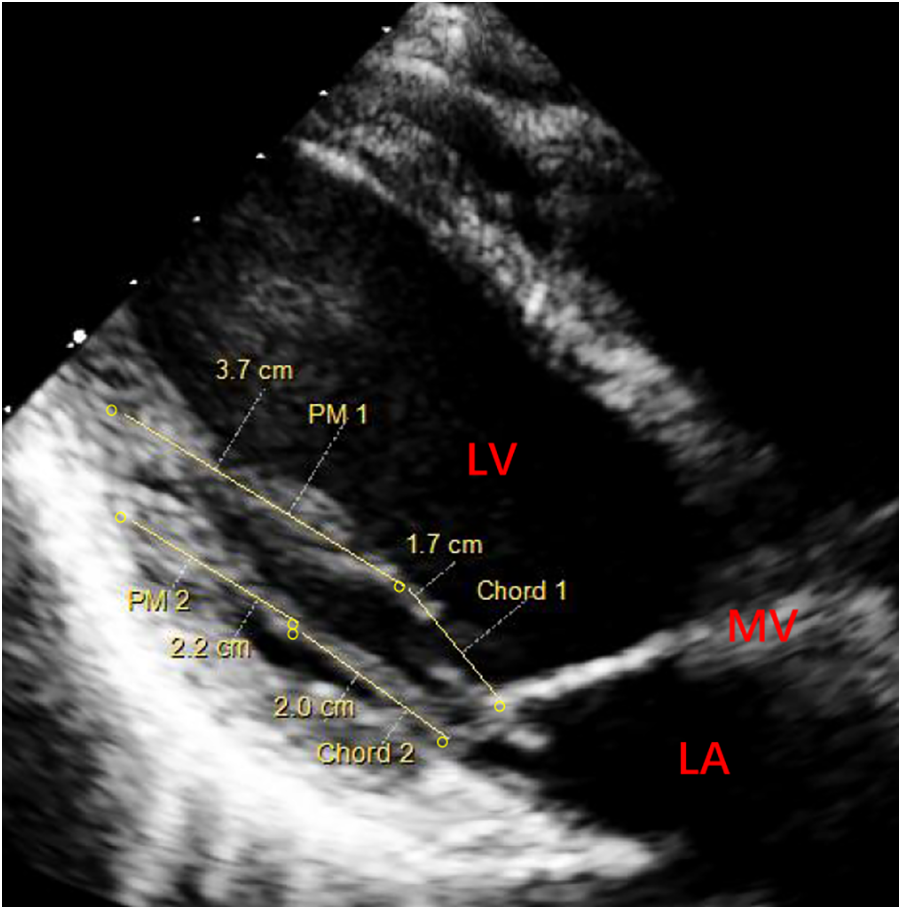

We conducted a case series of all patients diagnosed with mitral prolapse caused by PMs elongation through their preoperative echocardiography. According to their echocardiographic images, we measured the length of the chordae and papillary muscles during left ventricular systole (Figure 1). The length of PM was the distance from the endocardial surface at the left ventricular base to the fibrous head of PM. The length of the chord was the distance from the fibrous head of PM to the segment of the leaflet. Besides, we ruled out other heart diseases (such as coronary artery disease, congenital heart diseases, hypertrophic obstructive cardiomyopathy, etc.) based on the patient's echocardiography and laboratory findings. The registry collects comprehensive data on baseline patient characteristics, surgical details, in-hospital outcomes, and annual clinical follow-up.

Figure 1

Preoperative echocardiography (parasternal long-axis view) of left ventricular systole for measuring the length of papillary muscles. PM 1 (elongated PM, 3.7 cm) and Chord 1 (the chord of abnormal PM, 1.7 cm). PM 2 (normal PM, 2.2 cm) and Chord 2 (normal chord, 2.0 cm). PM, papillary muscle; MV, mitral valve; LA, left atrium; LV, left ventricle.